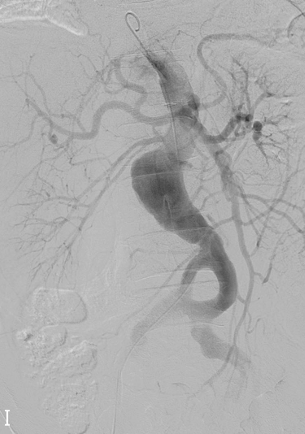

Fig 2I

(I) Final aortography showed even contrast flow at both true and false lumen, which meant the technical success of aortic fenestration.